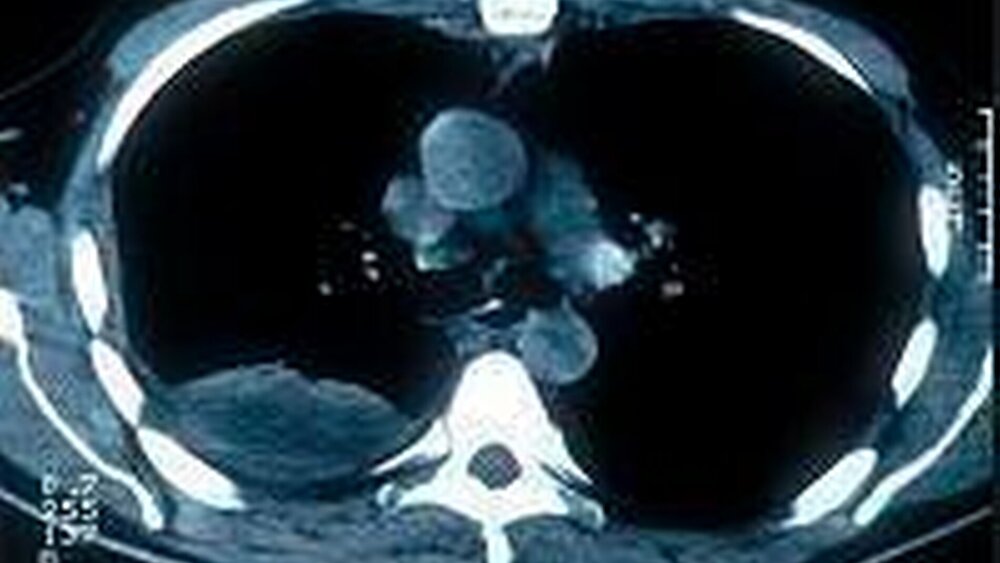

Die nach Verlegung auf eine Intensivstation veranlasste Röntgenaufnahme des Thorax und das nachfolgende CT zeigten ein Mediastinal- und Pleuraempysem (Abbildung 3). Die Residualbefunde der Abbildung 4 zeigen die Rückbildung der Thoraxbefunde nach Pleuradrainage zum Ende der dreiwöchigen Intensivbehandlungsphase. Der Patient überlebte ohne bleibende Folgeschäden.